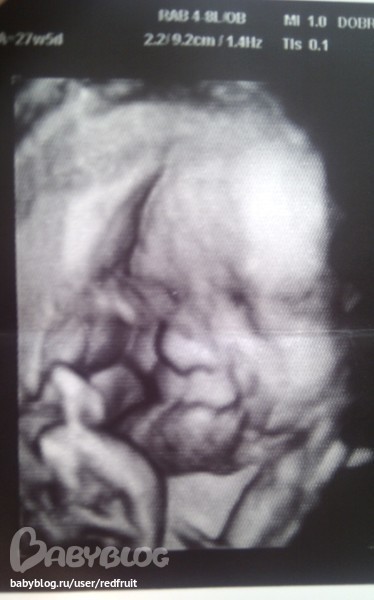

А последние фотки малыша такие, 27 недель и 5 дней:

но все равно видно, что похож на папу) Еще нам на память записали "лучшие фрагменты" на видео))